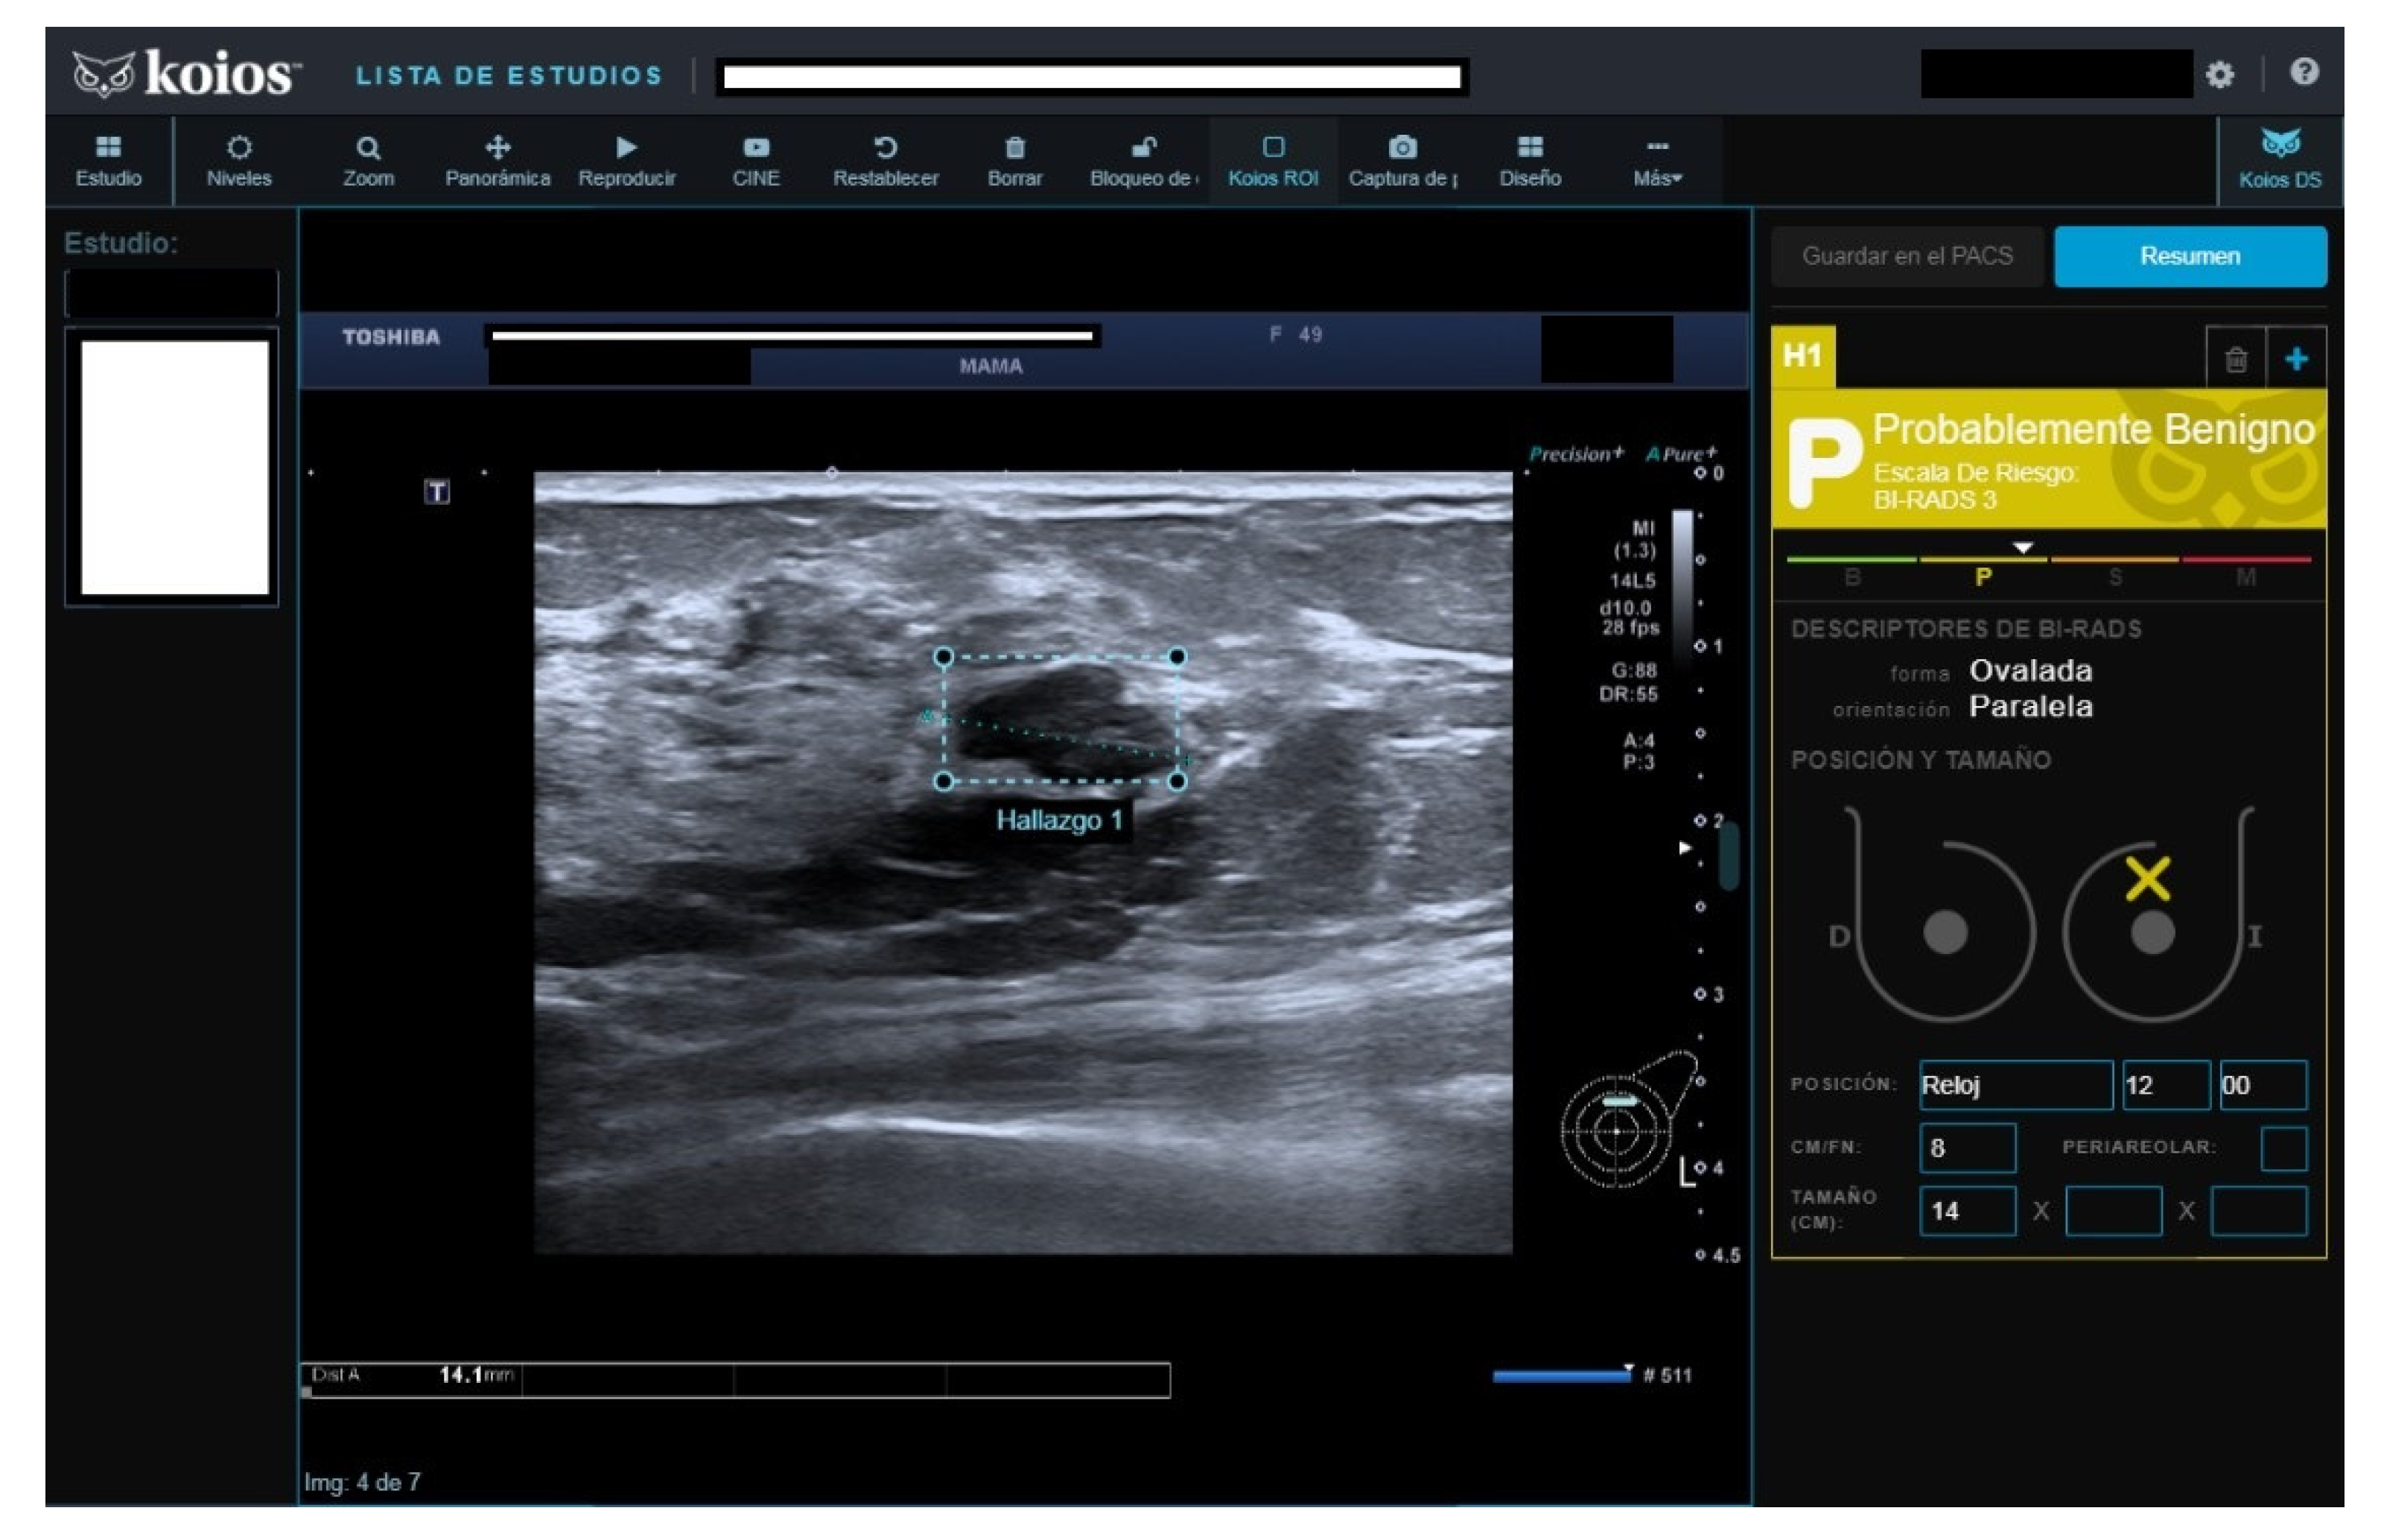

Figure 3.

Nodule rated B3 by reader, Kpb by KOIOS. Cytology reported fibroadenoma with simple hyperplasia; biopsy rendered a fibroadenoma diagnosis.